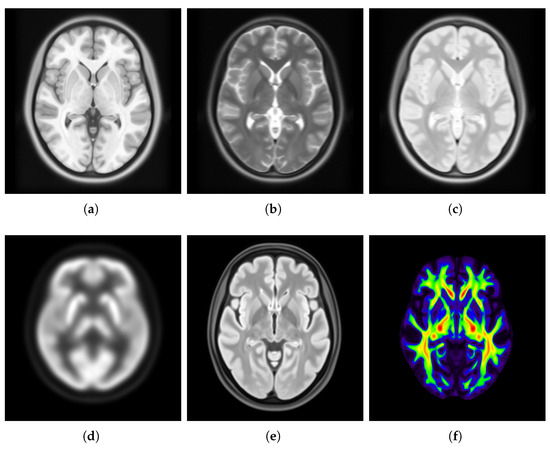

3.4.3. Usability of Saudi Brain Template

4.3. Usability of Saudi Brain Template

- Incorporating multiple imaging modalities (e.g., T2-weighted MRI, CT, fMRI, PET, DTI) to enhance both anatomical and functional relevance of the templates.